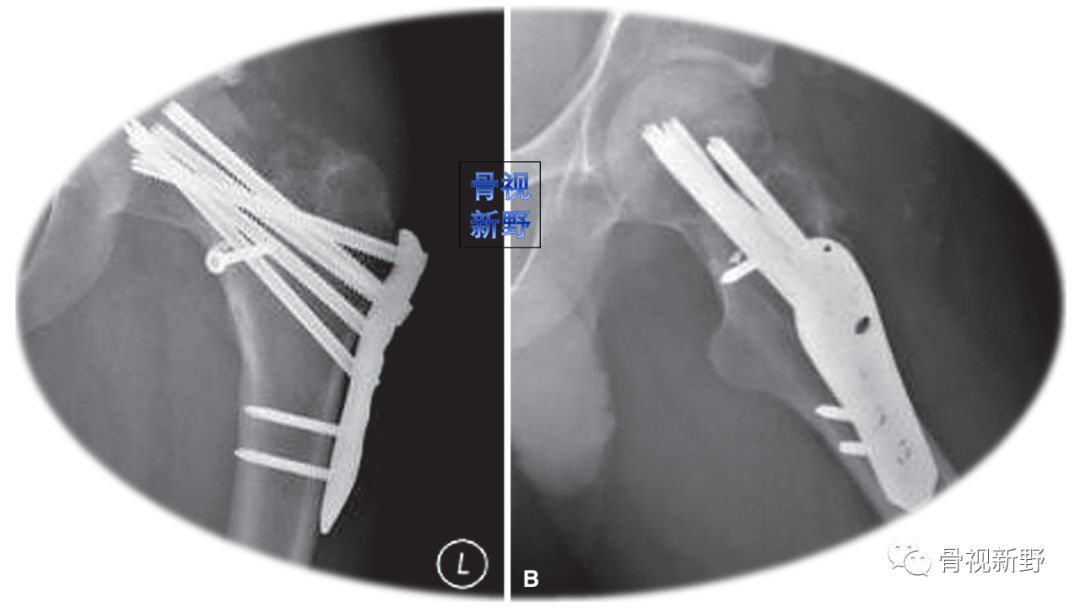

传统固定理念——角翼钢板(blade screw)

较少使用,偶用于翻修和外翻截骨固定。

上图股骨颈骨折空心钉固定失败,内翻畸形、不愈合。行转子间外翻截骨翻修术改用角翼钢板固定(坎贝尔12版,pp2736)。